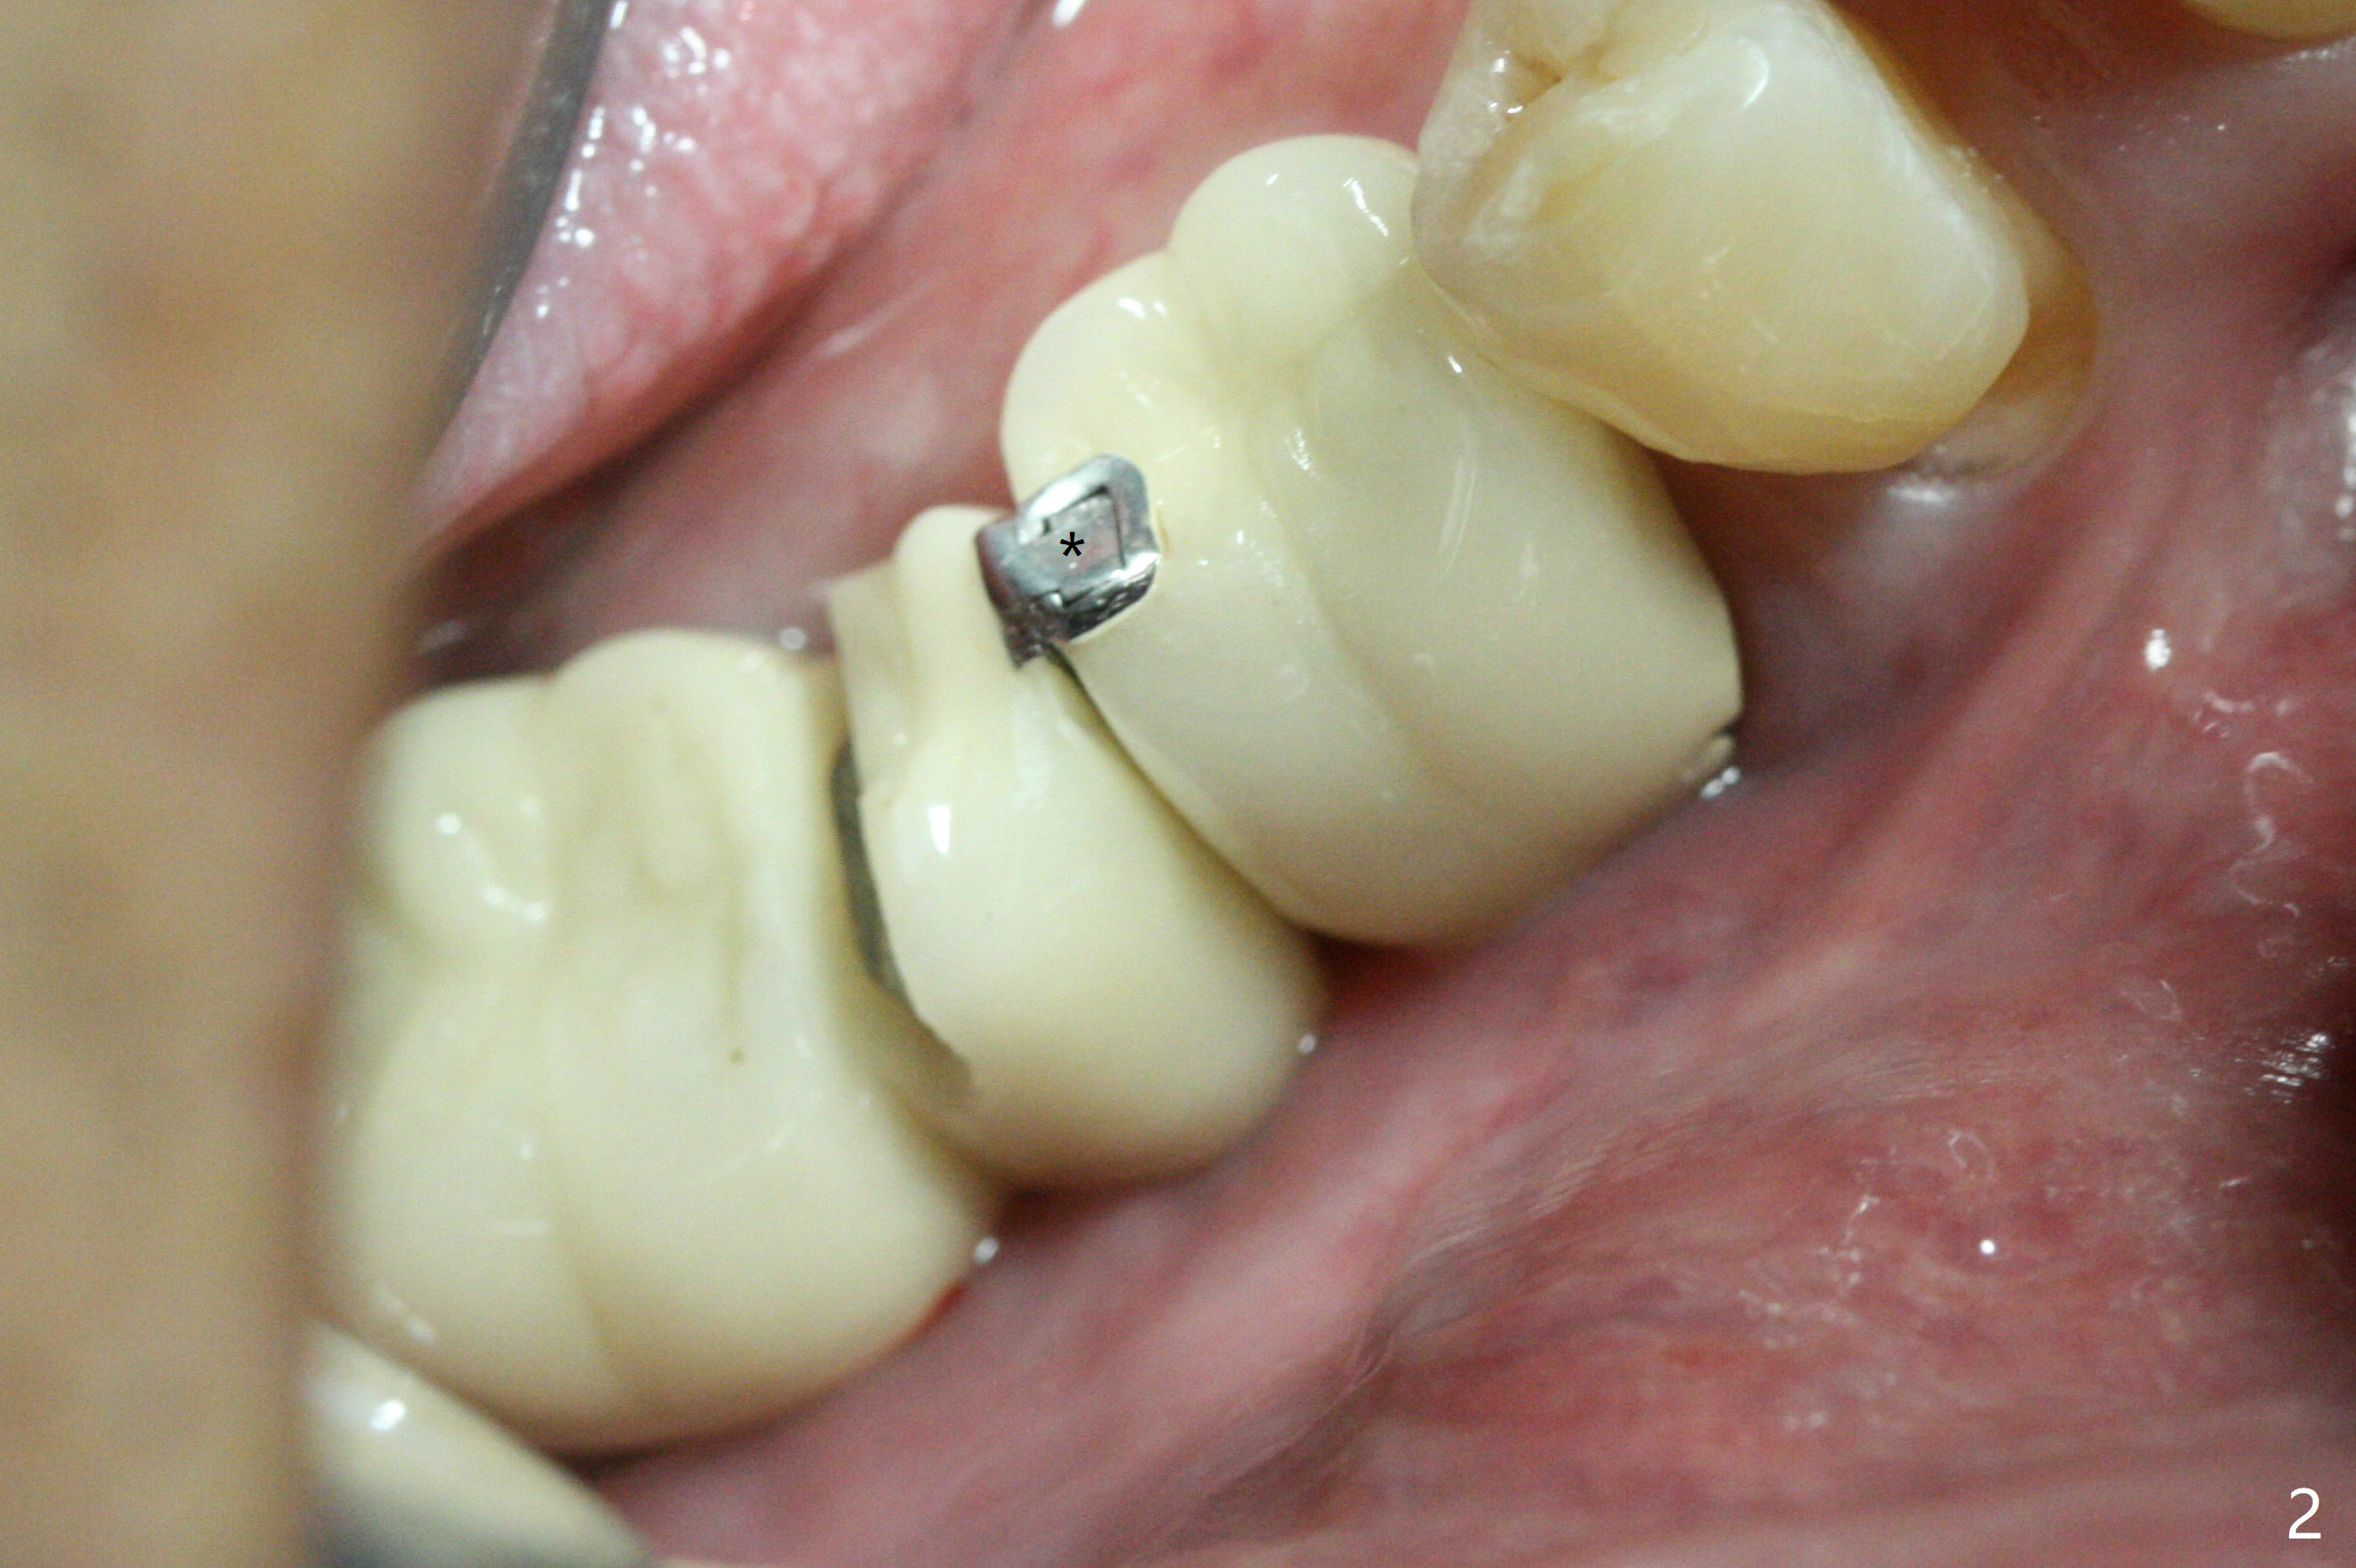

There is a space underneath the pontic at #30 (Fig.1 *), the basis for food impaction. After sectioning between the pontic and the posterior retainer, the pontic is removed from the anterior retainer with an attachment (Fig.2 *). The initial depth of osteotomy is 10 mm following ridge top reduction (Fig.3). A 3x10(4) mm 1-piece implant is placed with >50 Ncm; to reduce possibility of crown dislodgement from the implant, the retainers will be kept with modification of the proximal surfaces as shown by curved lines in Fig.4. Periodontal dressing is applied after suturing. There is no postop paresthesia. The periodontal dressing remains in place 2 weeks postop because of engagement into the attachment slot and undercuts (Fig.5). The patient returns 3 months postop; after minor contour adjustment (Fig.6 red curved line), impression is taken. The permanent crown is temporarily cemented (3.5 months postop) in case of food impaction due to the distal overhang of the tooth #29 (Fig.7). In fact the patient returns 4.5 months post cementation with right TMD (muscle relaxant prescribed) and food impaction, although there is no bone resorption (Fig.8,9). It appears that the crown at #29 needs to be redone, while porcelain will be added to the mesial surface of the one at #30 (Fig.10 red lines). In fact the crown at #30 is redone because of loose proximal contact with #31; there is no bone resorption 13 months post cementation (Fig.11). Bone resorption remains unnoticeable 28 months post cementation (Fig.12,13).